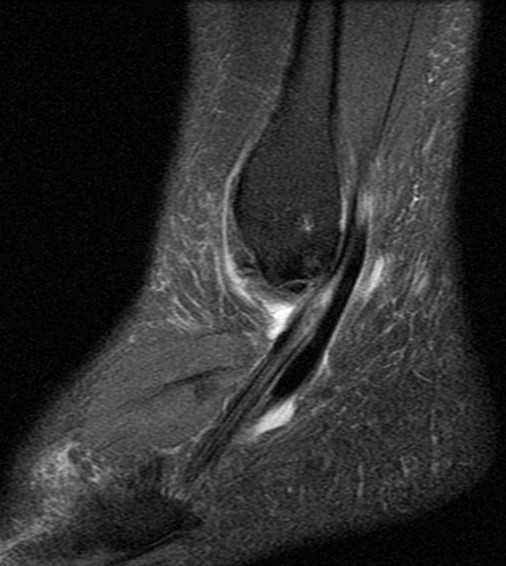

Figure 4 for case Peroneus brevis split tear

Figure 4

41 y/o avid bowler. Nice split tear from the lateral malleoulus tip down past the peroneal tubercle. Reactive tenosynovitis.

Peroneus brevis split tear